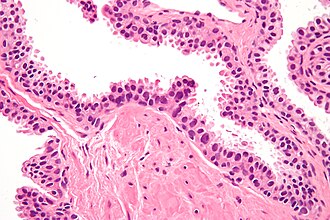

Template:Px High-grade prostatic intraepithelial neoplasia. H&E stain. | |

| LM | nuclear changes (hyperchromatic nuclei, nucleoli present, +/-increased NC ratio, mild-to-moderate nuclear enlargement), medium-to-large glands with the architecture of HGPIN (tufted, micropapillary, flat) |

- Medium to large glands with architectural changes - see HGPIN architecture below.

- Described as "epithelial hyperplasia".

- Diagnosed on basis of nuclear changes.

- Hyperchromatic nuclei - key (low power) feature.

- Nucleoli present - key (high power) feature.

- Often increased NC ratio.

- Nuclear enlargement - usually subtle/appreciated at high magnification only.

- Tinctorial changes of the cytoplasm - usually amphophilic (red) or basophilic (blue).